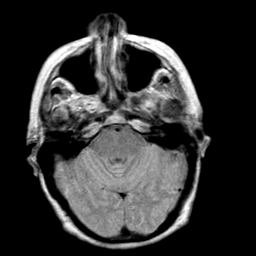

Creutzfeld-Jakob disease: proton density-weighted MR -- Slice #6

[Home][Help][Clinical] Slice 6